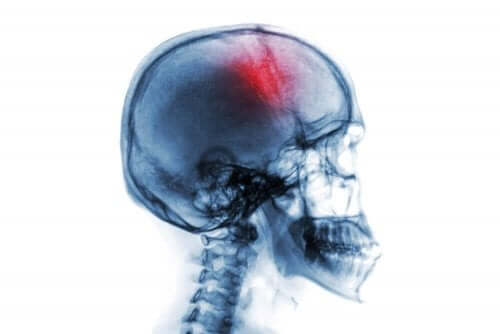

Et hjerneslag er et brått nevrologisk syndrom som kommer med mange risikofaktorer og symptomer. Det innebærer enten blødning eller tap av blodsirkulasjon i hjernen. I dag skal vi se på risikofaktorer og symptomer på hjerneslag

Når blodtilførselen ikke når hjernen ordentlig, begynner hjernevev å dø. Dermed resulterer det i et nevrologisk underskudd som kan føre til uførhet eller til og med død.

- “Ictus” eller “slag”. Dette innebærer en stopp av blodstrømmen i hjernen. For det første kan det være forårsaket av en hindring i noen av blodårene som forsyner hjernen (iskemi). Dette er vanligvis relatert til ateroskleroseproblemer. For det andre kan det skyldes intracerebral blødning eller hemoragisk hjerneslag.